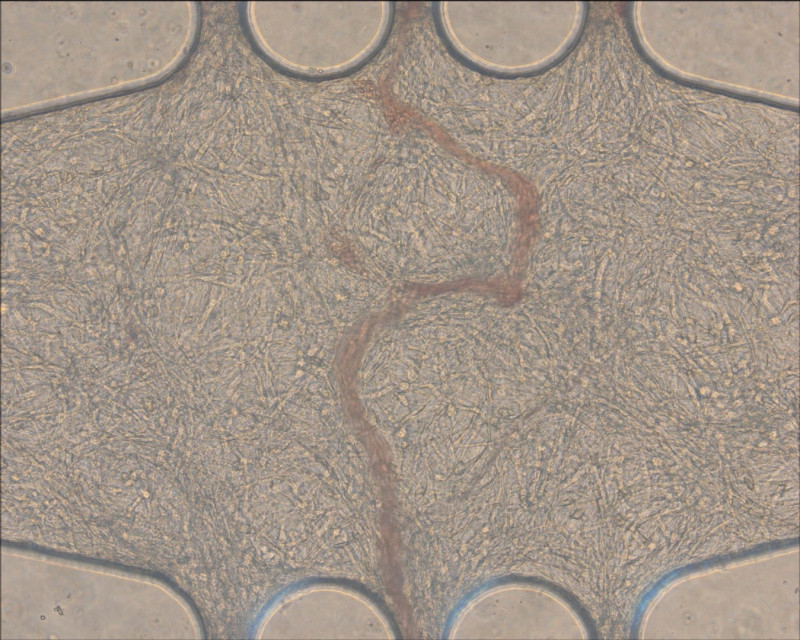

許聿翔表示,團隊研究心臟器官晶片,關鍵是心肌細胞培養,傳統培養皿作法,其細胞排序紊亂,跳動的同步性低,需好幾個月至半年,才能達模擬心跳的同步化,團隊透過溝槽結構與細胞力學,加上特殊基材,「騙」心肌細胞如在體內環境,僅14天到15天左右,就達同心圓收縮的同步化,可進行後續測試心臟藥物。

「機械也可結合生醫!」許聿翔說,該心臟晶片還結合壓電材料,讓心肌細胞跳動訊號直接轉成電訊號,讓心跳頻率免用高解析度顯微鏡觀察,直接用機器偵測心跳頻率,輸出心肌收縮波形,目前更搭配檢測業界的格式,已開發多孔盤自動化監測系統,有別其他晶片一次測1種藥,團隊設計一盤可塞3種藥,大幅提高新藥測試效率。